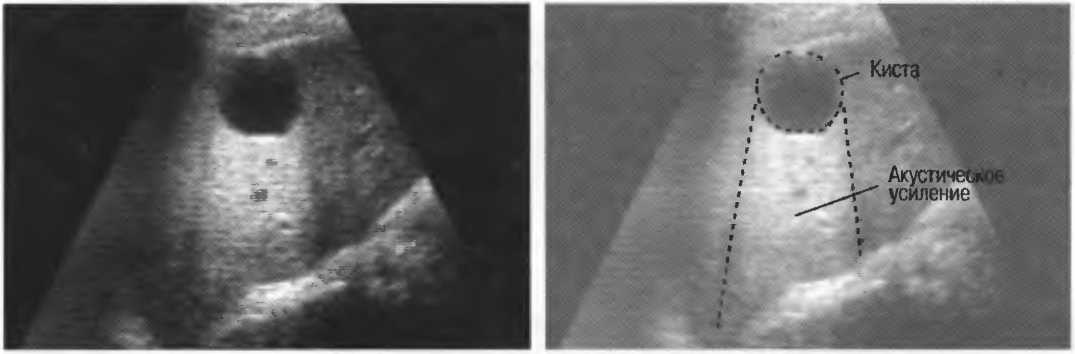

Кисты

Киста, как правило, визуализируется в виде анэхогенной зоны, при этом структуры, расположенные за кистой, обычно усилены: полость кисты анэхогенна, поскольку в ней нет структур с различным акустическим сопротивлением. В результате того что жидкость не поглощает ультразвук в такой же степени, что и ткань, эхо-сигналы от расположенных позади кисты структур гиперкомпенсированы сканером и выглядят усиленными — появляется эффект усиления задней стенки (рис. 14а,б).

Киста определяется в виде анэхогенной зоны с усилением по задней стенке. Если в кисте есть внутренние зхоструктуры, то они могут быть реальными или являться артефактами.

Рис. 14а. Заполненная жидкостью киста: полость кисты анзхогенна, имеется усиление задней стенки.